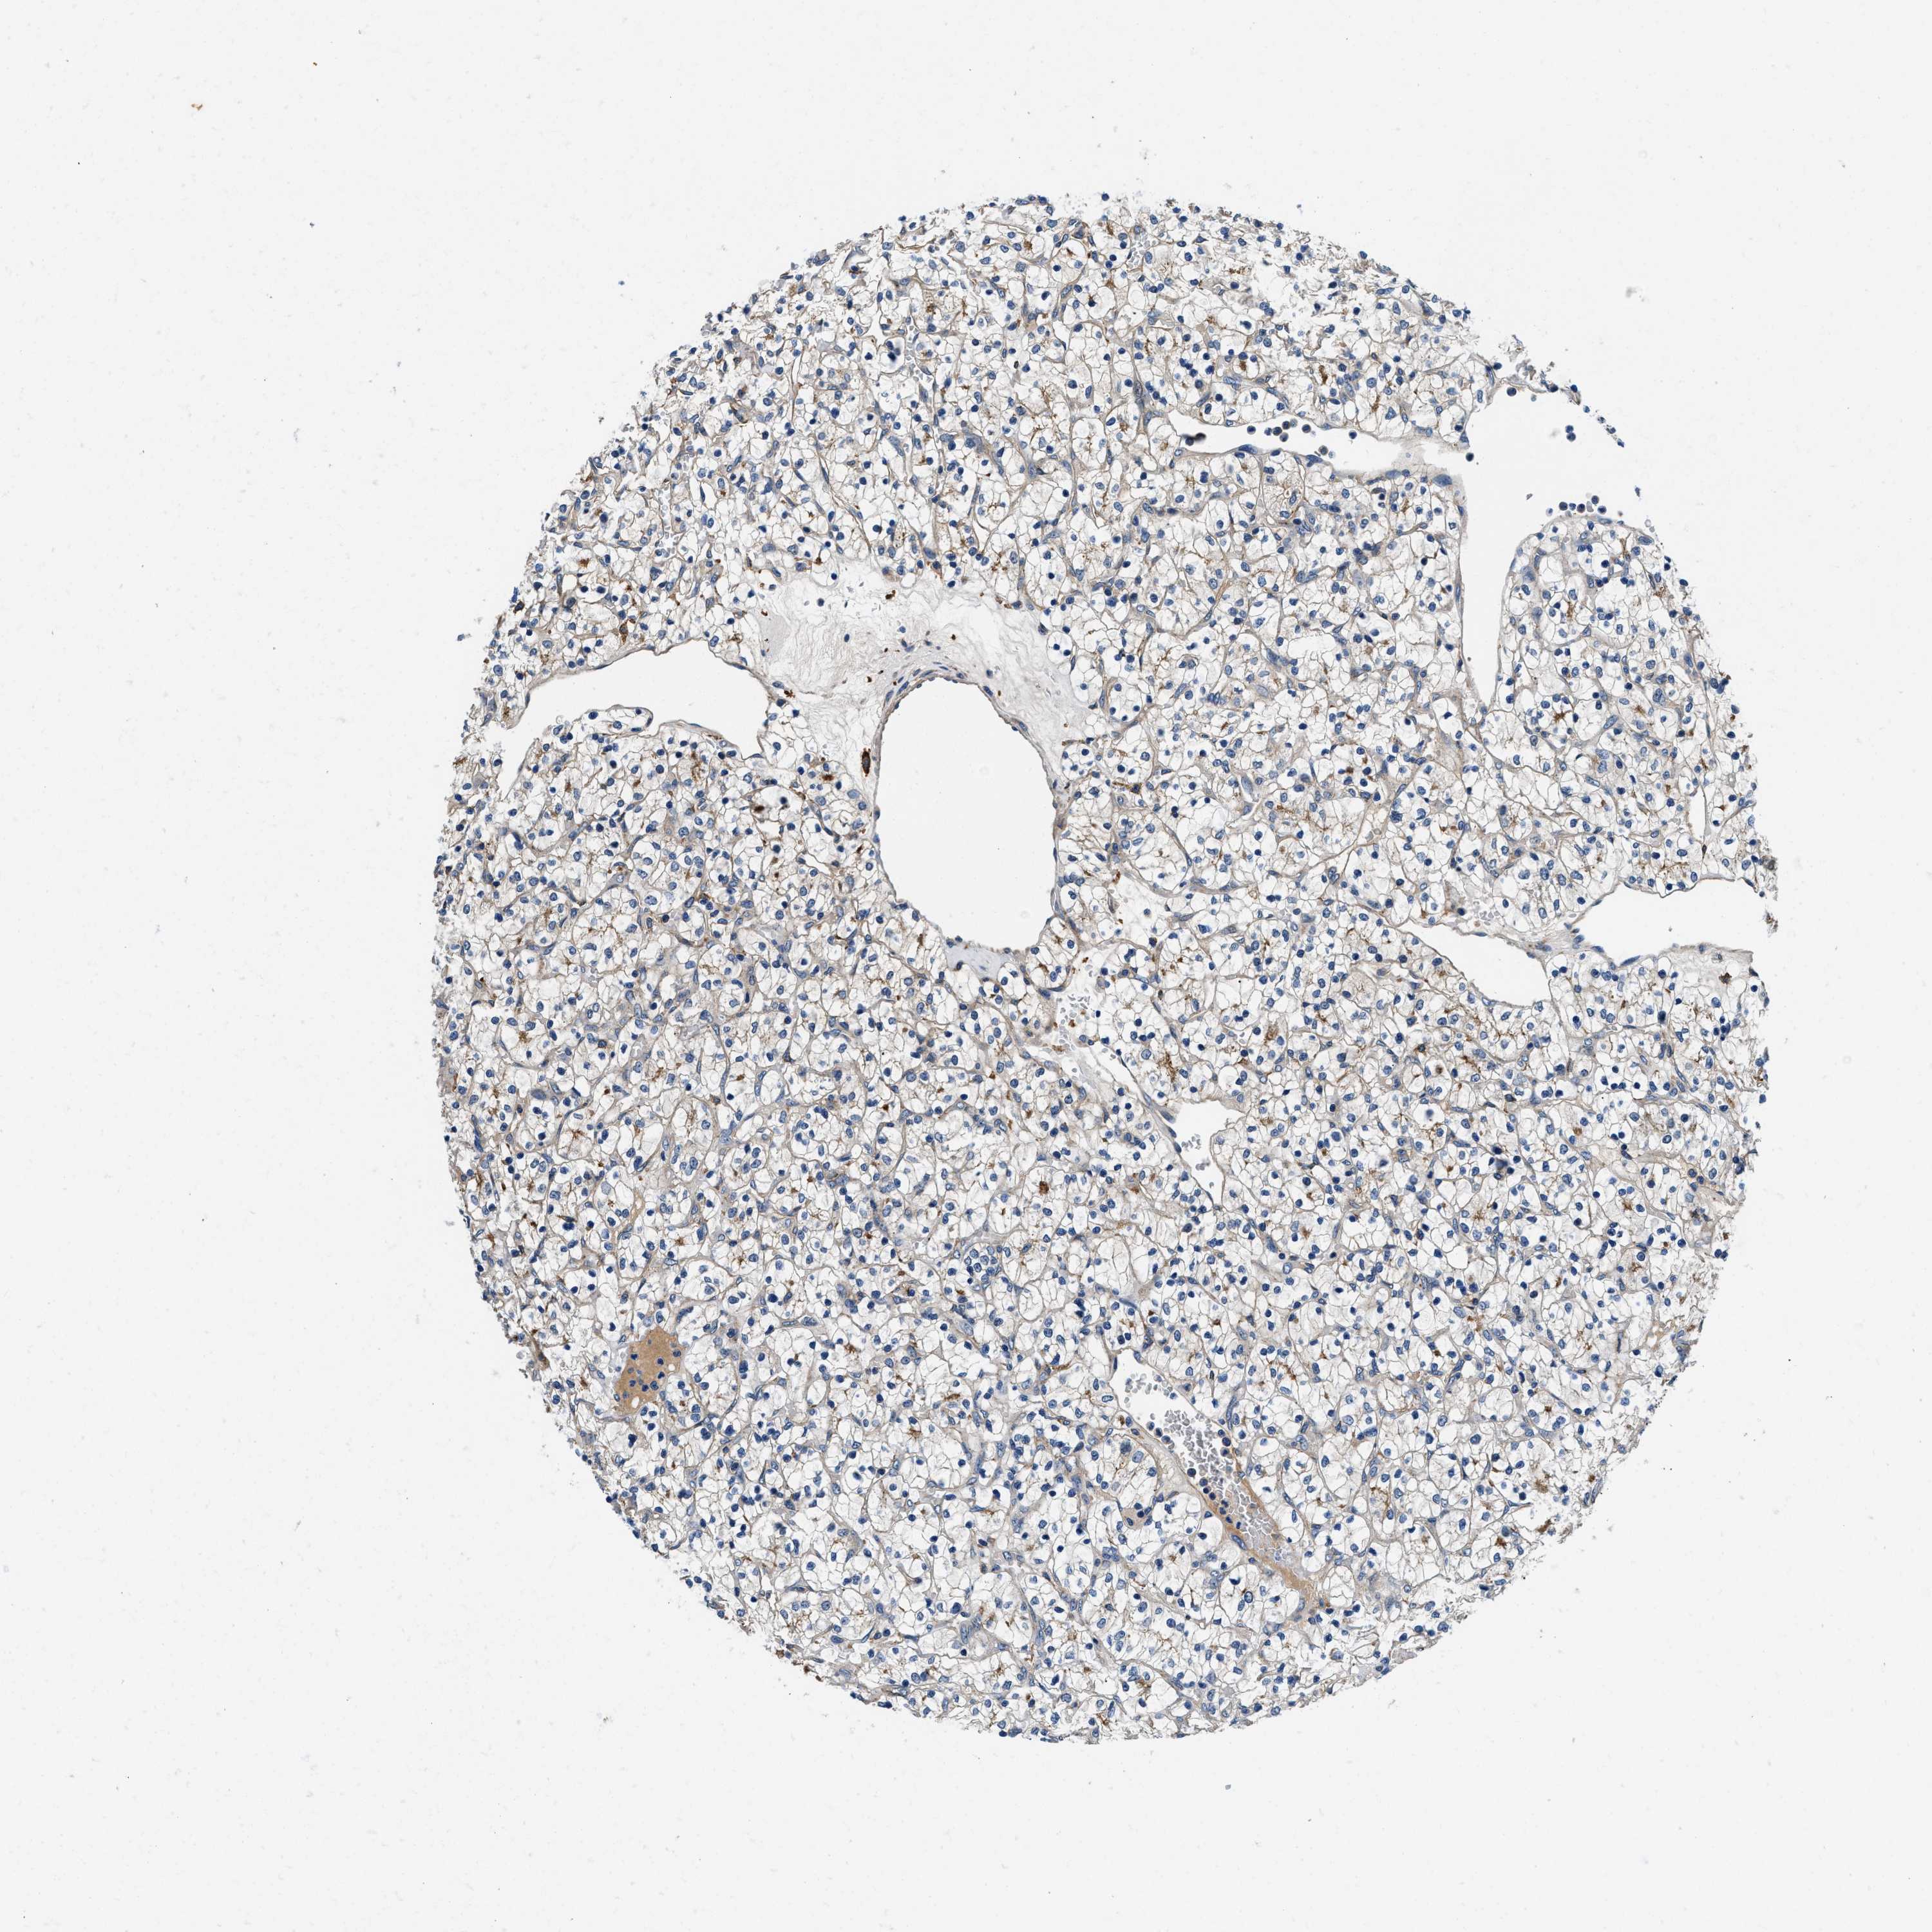

KIDNEY RENAL PAPILLARY CELL CARCINOMA (TCGA) - Interactive survival scatter ploti

The Survival Scatter plot shows the clinical status (i.e. dead or alive) for all individuals in the patient cohort, based on the same data that underlies the corresponding Kaplan-Meier plots. Patients that are alive at last time for follow-up are shown in blue and patients who have died during the study are shown in red.

The x-axis shows the expression levels (FPKM) of the investigated gene in the tumor tissue at the time of diagnosis. The y-axis shows the follow-up time after diagnosis (years). Both axes are complimented with kernel density curves demonstrating the data density over the axes. The top density plot shows the expression levels (FPKM) distribution among dead (red) and alive patients (blue). The right density plot shows the data density of the survived years of dead patients with high and low expression levels respectively, stratified using the cutoff indicated by the vertical dashed line through the Survival Scatter plot. This cutoff is automatically defined based on the FPKM cutoff that minimizes the p-score. The cutoff can be changed by dragging the vertical line or by entering a cutoff value in the square labeled "Current cut-off".

Under the Survival Scatter plot the p-score landscape (black curve; left axis) is shown together with dead median separation (red curve; right axis). Dead median separation is the difference in median mRNA expression between patients who have died with high and low expression, respectively. It is calculated as follows: median FPKM expression of dead patients with high expression - median FPKM expression of dead patients with low expression. This is intended to aid the user in visually exploring custom cutoffs and the associated p-scores and dead median separation.

Individual patient data is displayed and can be filtered by clicking on one or more of the category buttons on the top of the page. Categories describing expression level and patient information include: high, low, alive, dead, female, male and tumor stages. The scale of the x-axis can be toggled between linear and log-scale by clicking on the "x log" button. Mouse-over function shows TCGA ID, patient information and mRNA expression (FPKM) for each patient.

& Survival analysisi

Kaplan-Meier plots summarize results from analysis of correlation between mRNA expression level and patient survival. Patients were divided based on level of expression into one of the two groups "low" (under cut off) or "high" (over cut off). X-axis shows time for survival (years) and y-axis shows the probability of survival, where 1.0 corresponds to 100 percent.

ZFAND3 is not prognostic in Kidney Renal Papillary Cell Carcinoma (TCGA)